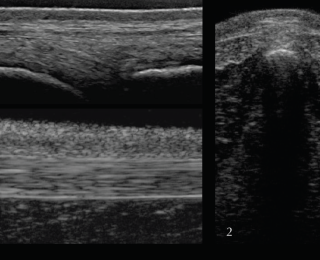

For the supra- and interspinous ligaments (SSL and ISL) longitudinal views are most useful. The images are best acquired with a high-frequency linear transducer using a stand-off pad. The head should be kept in a neutral position as high head carriage may cause relaxation of the SSL and therefore a hypoechogenic appearance. Superficial fibres of the SSL have a horizontal orientation whereas deep fibres of the ISL run in caudoventral direction appearing hypoechogenic in comparison. Care should be taken to position the probe exactly midline at the level of the dorsal spinous processes. The aponeuroses of the epaxial musculature can be imaged off-midline with a parallel fibre pattern similar to the SSL.

In the thoracic (saddle) region the SSL is thin and wide, whereas further caudal in the lumbar region the ligament is thick and narrow with a more echogenic, homogenous appearance. The transverse view of the SSL is less useful due to being more prone to artifacts. In order to achieve the best image quality, the transducer should be tilted cranially and caudally. Published scientific data about the ultrasonographic appearance of the SSL in normal horses and horses with back pain offering information about the potential clinical significance is limited (Henson et al 2007). The clinical significance of heterogenous regions in the SSL should therefore be questioned and further tests, such as diagnostic local anaesthesia, should be applied.

Deep to the ligament the fibrocartilaginous cap, visualised as a hypoechogenic line of approximately 1mm, is visible and runs parallel to the hyperechoic line of the DSP bone surface. The ISS cannot be assessed fully and a statement about potential iminging DSPs should not be made based on ultrasonography alone. The intervertebral articulations can be examined ultrasonographically, both in sagittal and frontal planes, using a convex transducer (Denoix 1999a; Reisinger and Stanek 2005).